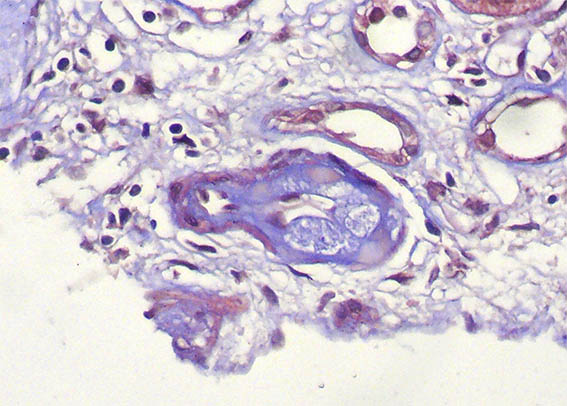

Figure 5. Masson´s trichrome, X400.

Figure 9. Masson´s trichrome, X400.